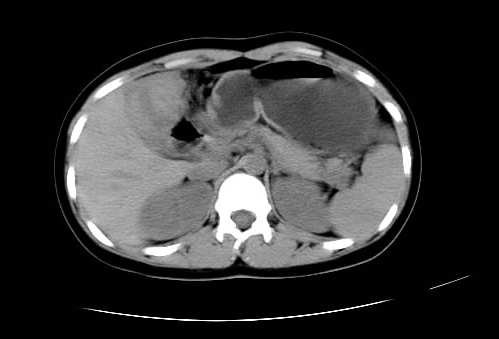

女 16岁  右上腹痛一天,无其他不适

肿块最大径位于十二指肠降段与水平段移行处,并且与肝脏压迹呈“0”形征,可以考虑位于肝外并与胃肠道关系紧密,考虑胃肠道间质瘤(gist)可能较大,须除外神经节起源肿瘤。

肿块与十二指肠关系密切,支持间质瘤诊断.肝脏与结肠均为受压改变.

右下腹巨大肿快,密度不均匀,内见坏死低密度区,边界清楚,与周边胀器明显有分界,未见强化,多考虑来源于间叶组织的良性肿物.

病灶巨大,少部分向肠腔内生长,大部分向长腔外生长。其密度不均匀,增强显示明显不均匀强化,并见有大片状始终不强化的不规则坏死液化区。虽然病灶中上部形态尚可,病人又如此年轻,但中下部形态、密度、强化特点强烈提示为恶性病灶。综上,我考虑本病例为:恶性胃肠道间质瘤。